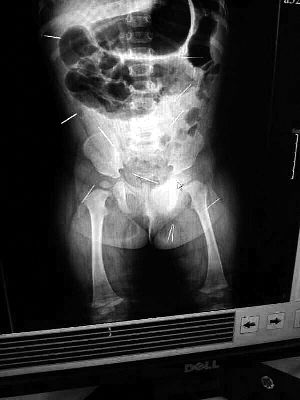

山東聊城11個(gè)月女嬰萱萱(化名)疑似被人以12根鋼針插滿臀部、腹腔等部位,昨天在兒童醫(yī)院會(huì)診后,醫(yī)生稱3根針靠近胸腔最危險(xiǎn),首批先行取出,預(yù)計(jì)將在下周二手術(shù)。孩子父母稱孩子一直由家人照顧,自家與他人并無冤怨。山東警方表示正在偵破中,不便透露案情。

“要不是當(dāng)初那幾個(gè)紅點(diǎn),可能到現(xiàn)在我們還不知道孩子身體里有鋼針!”昨天,在兒童醫(yī)院住院處,萱萱爸爸范先生稱,日前原本很愛笑的萱萱突然變得有些焦躁,一抱起來就哭,孩子母親偶然間在萱萱屁股上發(fā)現(xiàn)了幾個(gè)小紅點(diǎn)兒,原以為是蚊蟲叮咬,就醫(yī)結(jié)果卻讓人不寒而栗?!搬t(yī)院拍出的片子上,萱萱的體內(nèi)有12根鋼針,插滿臀部、腹腔、骨盆等各個(gè)部位。”范先生介紹,因?yàn)殇撫樢焉钊塍w內(nèi),要是孩子不哭鬧,他們很難發(fā)現(xiàn)。

北京晨報(bào)記者了解到,目前體內(nèi)的12根鋼針多分布在孩子的臀部,一根在腹部,其余3根在胸腔附近,其中一根很接近心臟。“因?yàn)楹⒆犹?,醫(yī)生們害怕取針的時(shí)候?qū)λ斐蓚?,在胸腔附近?針可能會(huì)威脅她的生命”。